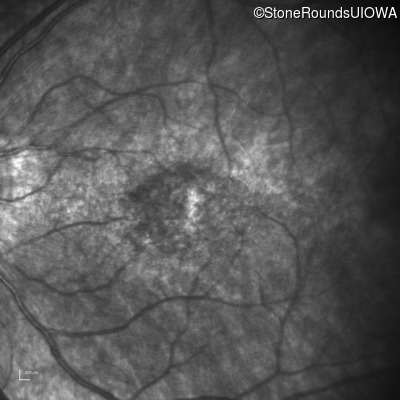

Infrared Fundus Photograph - Right - 20/80 -1

Exemplar

Infrared Fundus Photograph - Left - 20/100 -2